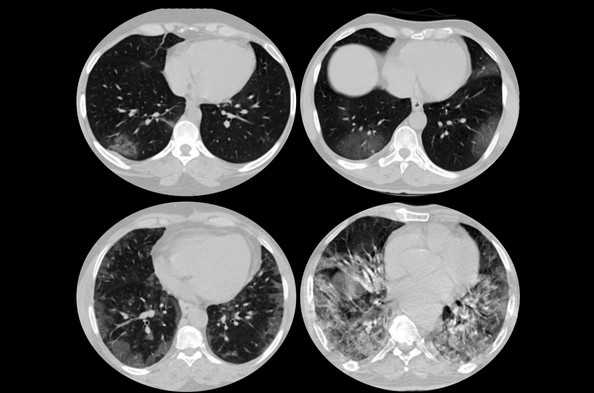

Метастатическое поражение легких

Вирусная (ковидная) пневмония на томограмме